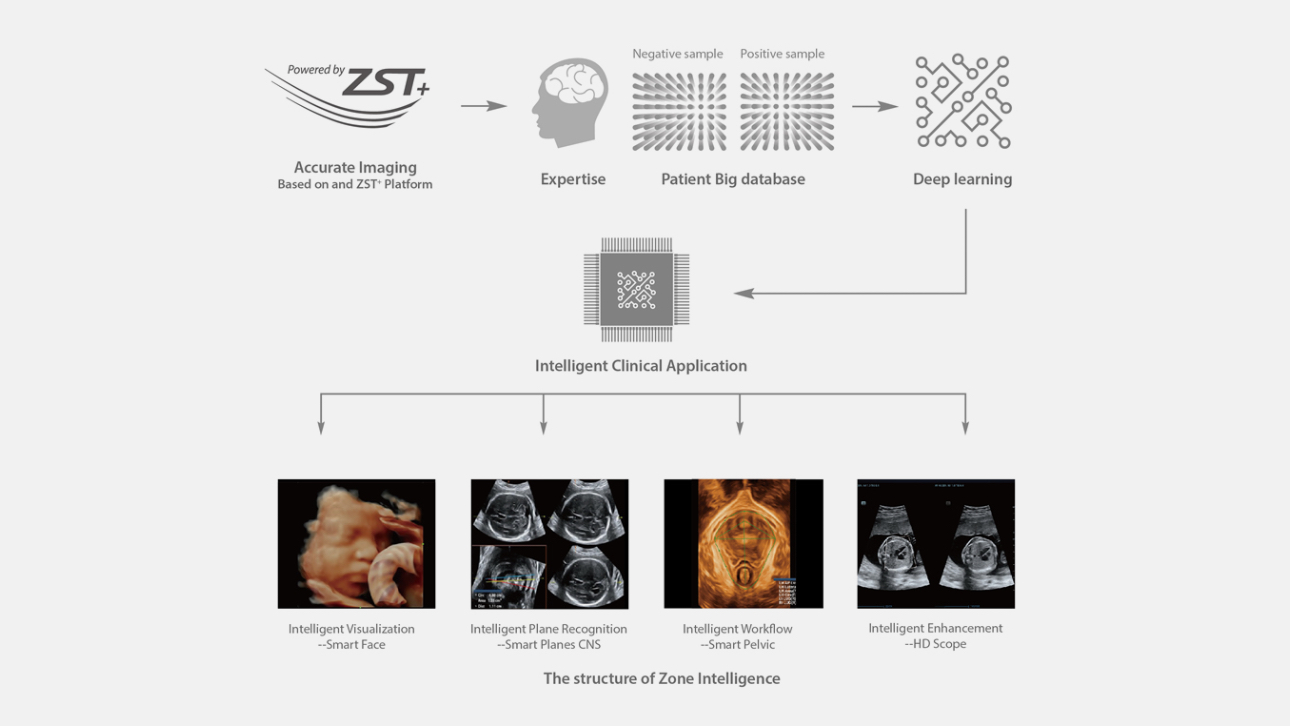

Since the company was founded, Mindray is continuously exploring new ways to improve diagnostic confidence. Powered by the most revolutionary ZONE Sonography? Technology, the ZST+ platform brings ultrasound image quality to a higher level by zone acquisition and channel data processing.

Thanks to the innovative, software-driven ZST+ platform, the Resona series is continuously evolving with the leading-edge technologies to meet the most challenging diagnostic demands in womenŌĆÖs health practice. More importantly, it is designed with the understanding that the wisdom of experts is always precious, and you need more intelligent partner for enhanced speed and confidence. Finally, Resona series with Zone Intelligence provides a total solution to help you with diagnostic confidence, efficiency, and standardization across different diagnostic challenges in todayŌĆÖs demanding and overburden hospital environment.